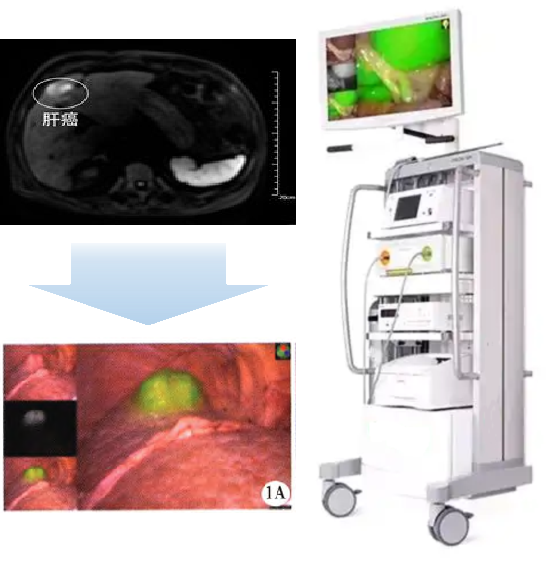

(二)适应症:本品拟用于原发性肝癌患者的术前诊断及术中导航。

PL002是浙江普利药业有限公司研发的荧光/磁共振双模态造影剂,开发荧光/磁共振双模态造影剂成为提高原发性肝癌手术效率的有效方案。双模态造影剂的荧光成像能力可用于肝癌术中荧光导航,而磁共振增强能力可用于在术前判断肝脏代谢能力,推测肿瘤及肝脏对造影剂的摄取情况,提高肿瘤诊断精度,降低术前规划难度。

PL002相较于吲哚菁绿具有明显优势。目前吲哚菁绿在临床使用中存在给药到手术时间不确定的问题,可能造成病灶与正常组织对比度不足,影响术中的病灶的判断,PL002采用独特的钆络合物与荧光分子共价键结合的分子结构设计,这种设计能够让医生在术前通过磁共振成像确定造影剂在病灶中的聚集情况,进而针对患者个体情况来对手术时间进行规划。同时,由于PL002体内更为稳定,在荷瘤小鼠模型中同等条件下荧光成像效果维持时间长于现有荧光造影剂,也保证了其在临床应用中具有更宽的手术窗口。

使用双模态造影剂可以为手术医生提供更加丰富的诊断信息,降低术中的决策压力,避免过度切成,增加发现微小病灶的可能性,最终实现患者的全面获益。此外,相较于传统荧光造影剂,PL002的安全性更高、体内更为稳定,成像效果更佳,为其临床使用提供了有效的支持。